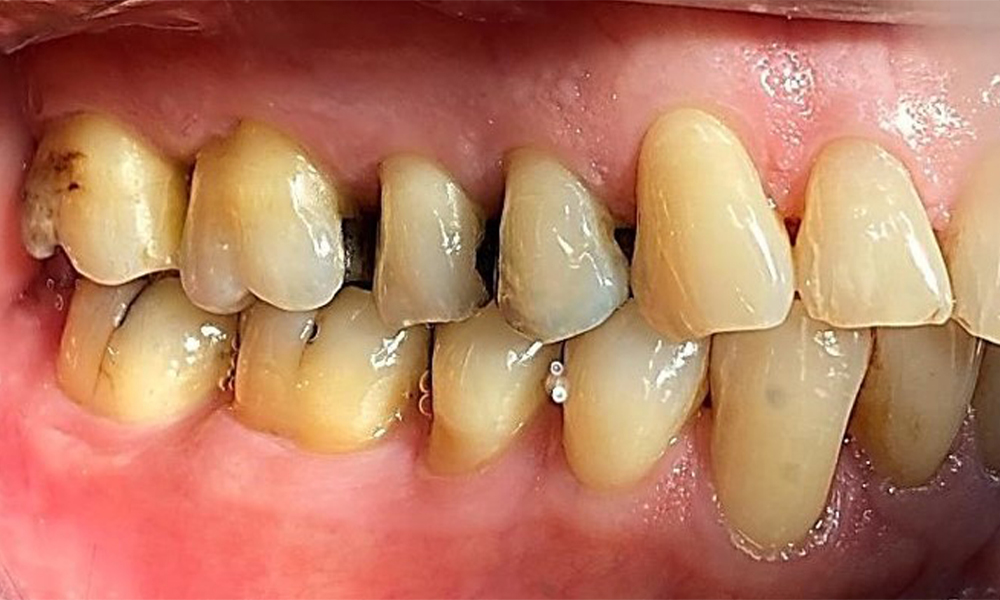

Right lateral view. Loss of the interdental papillae.

Fig. 3 Right lateral view. Loss of the interdental papillae. © Dr R. Krapf

Left lateral view including the recessions.

Fig. 4 Left lateral view including the recessions. © Dr R. Krapf

The patient has a full dentition with 28 teeth, which includes amalgam and composite fillings in the molar and premolar regions. There is a visible clinical marginal gap present on tooth 14. Tooth 27 has an adequate gold inlay. There are also generalized attritions and abrasions. (Fig. 2, Fig. 3, Fig. 4, Fig. 5, Fig. 6)

Periodontal findings

The patient has stage II, grade B periodontitis (5). At 1 to 3 mm, the clinical probing depths were within the physiological range. Localized probing depths of 5 mm were observed on the mesiopalatal aspects on both 17 and 27. There are generalized recessions of 1–3 mm with partial loss of the interdental papillae (Fig. 2, Fig. 3, Fig. 4)